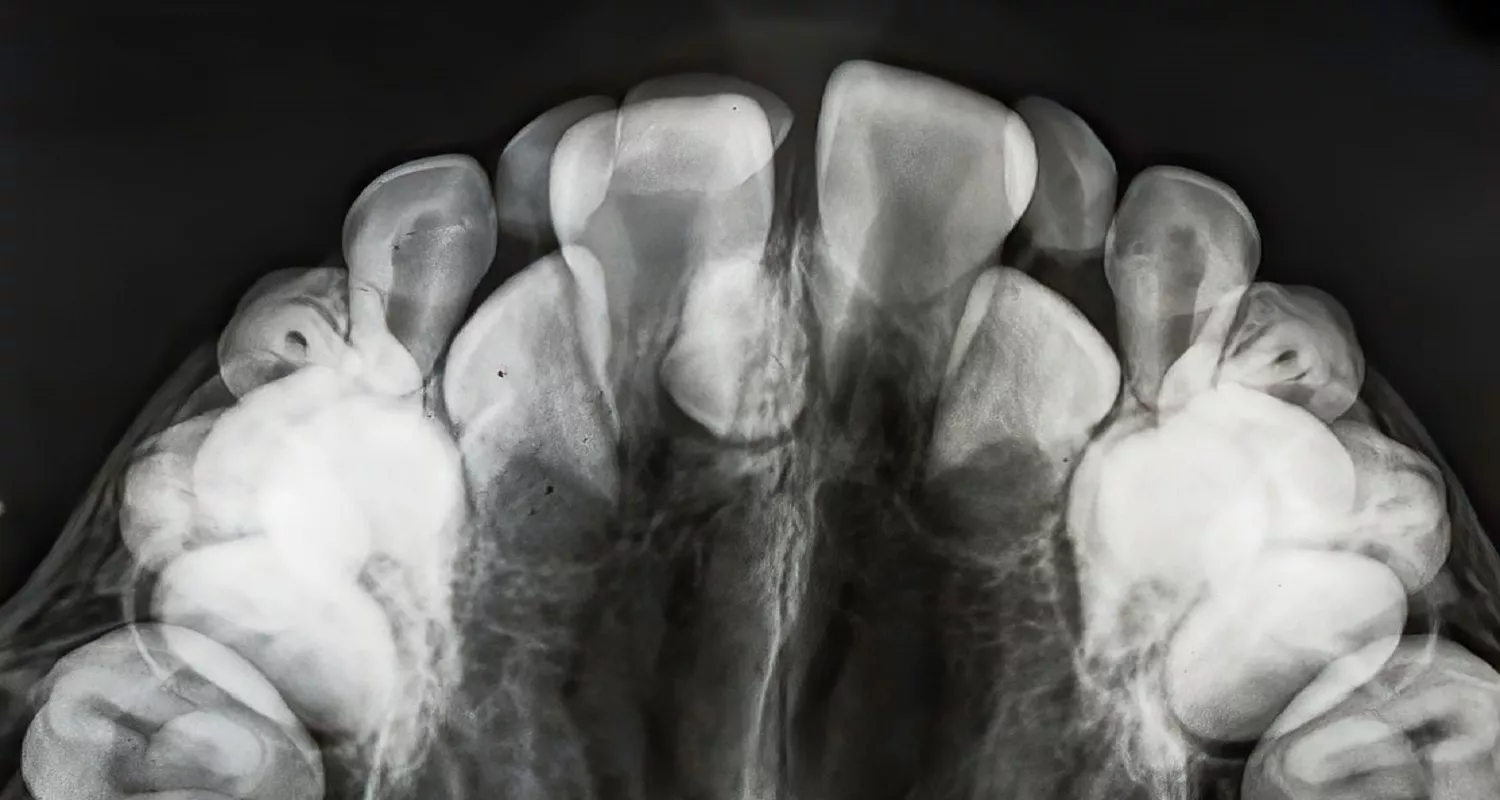

Algunos dientes extra salen a través de la encía (erupcionados), y otros quedan atrapados dentro de la mandíbula o el maxilar (impactados). Los dientes impactados solo se pueden ver con una radiografía dental.

- Radiografías dentales (panorámica o periapical): Son la herramienta más importante para encontrar dientes extra, especialmente los que no han salido todavía. Una radiografía panorámica da una imagen completa de todos los dientes y el hueso del maxilar.

- Tomografía computarizada (CT scan): En casos más complejos, se puede recomendar una tomografía 3D. Esto da una imagen muy detallada y ayuda al dentista a planificar el tratamiento con precisión.